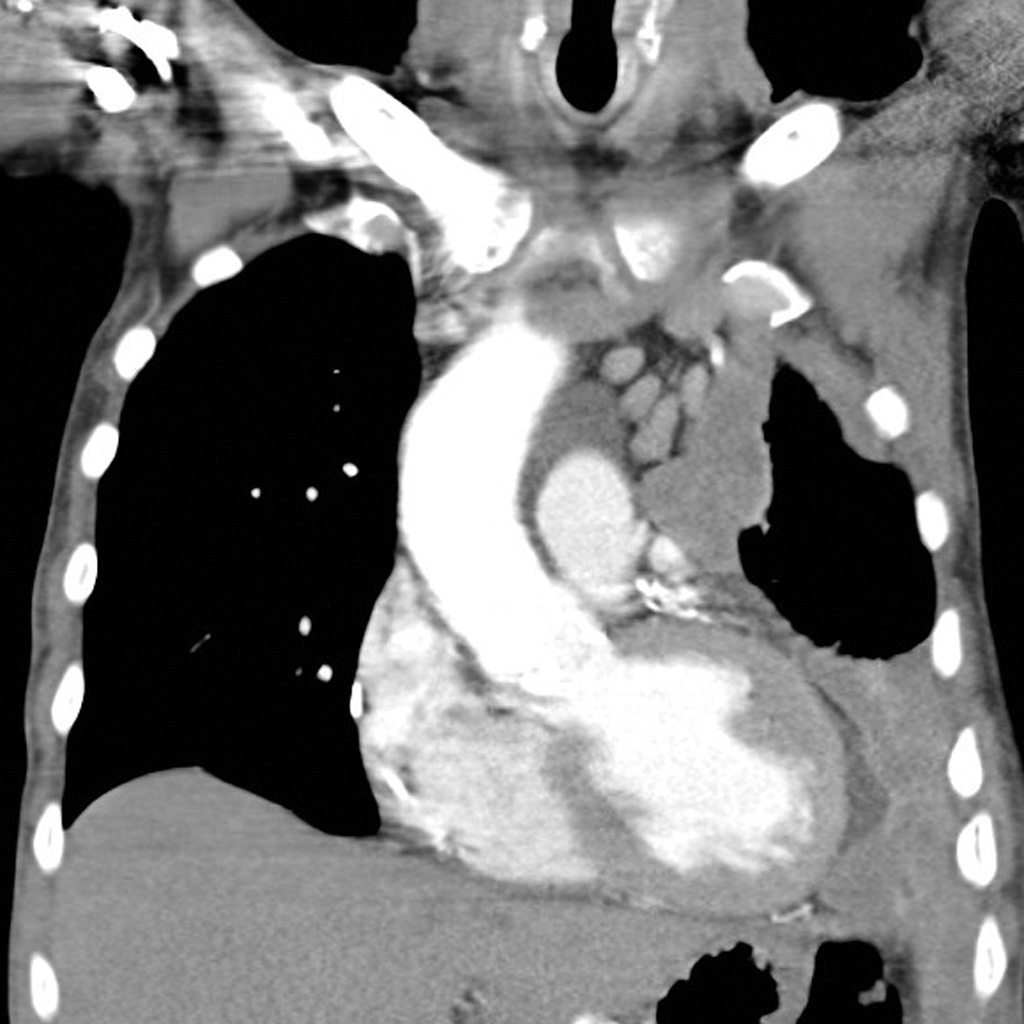

Because you refused the offered, mesothelioma killed you. Oh well.